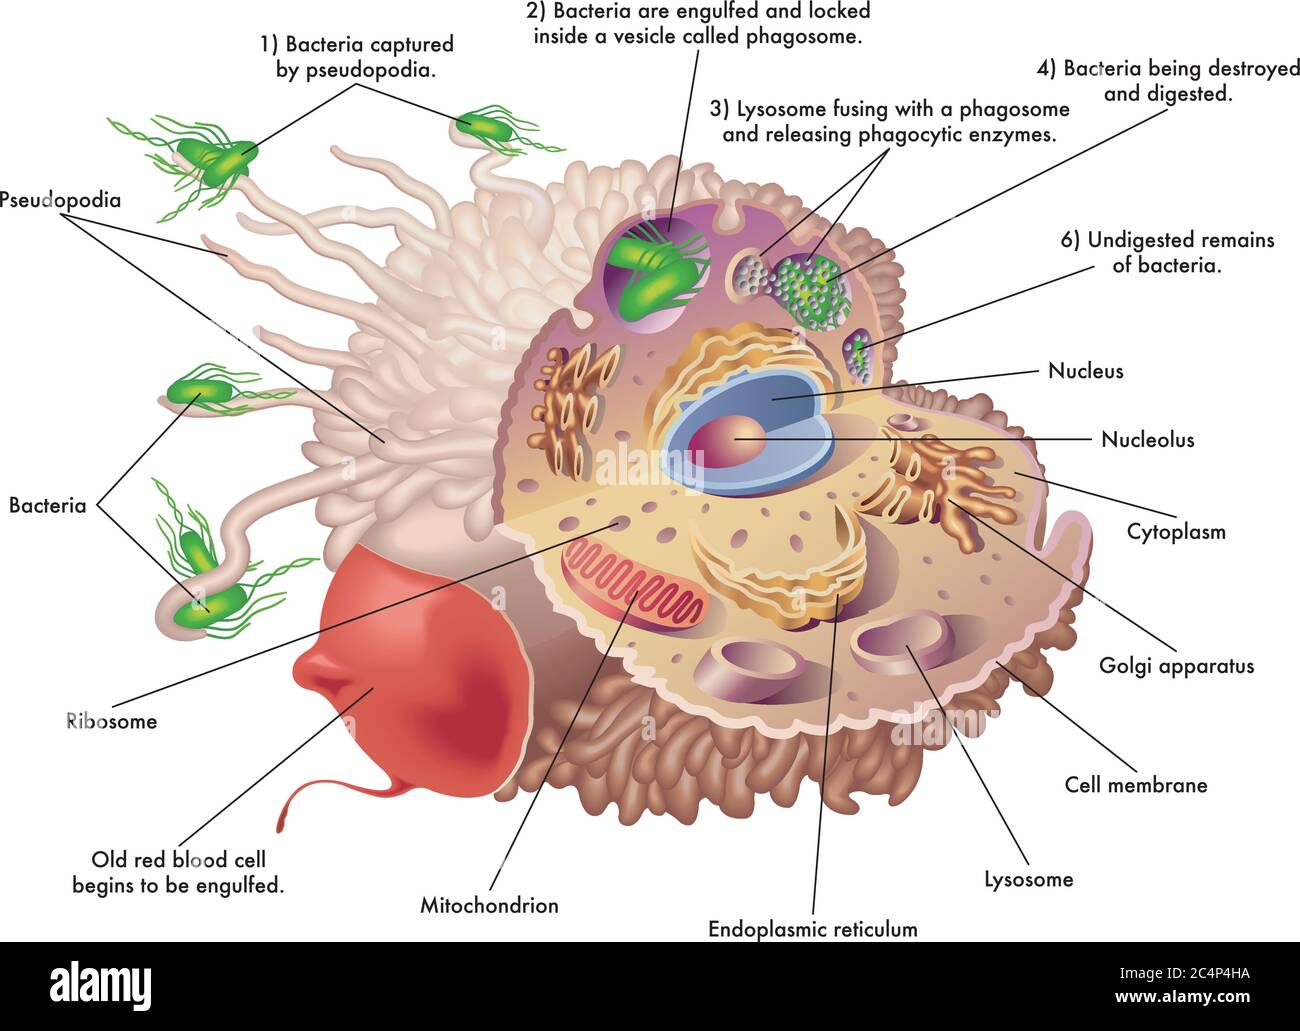

RF2C4P4HA–Illustrazione medica della struttura e della funzione di un macrofago, mentre si ingolfato un vecchio globuli rossi e batteri, mostrando come vengono catturati